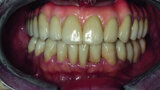

Fig. 27: Final prosthetic restoration in patients’ mouth.